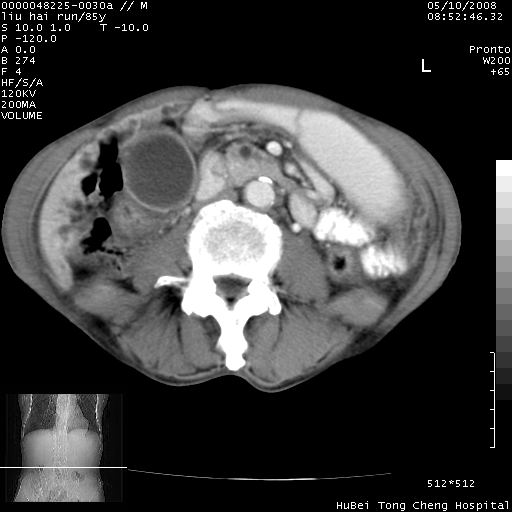

标题: CT13403:M,85Y。胆系低位梗阻。胰头占位?

彩超示胰头实质欠均匀,胰管扩张。

有“双管征”,胆总管胰头段突然中断,考虑为胰头癌。

影像表现:壶腹部扩张胆管呈截断样改变,肝内外胆管重度扩张,胆囊增大,胰管亦明显扩张,呈不规则患珠样,胰体尾部略有萎缩,增强扫描后壶腹部低密度影轻度强化,与钩突分界不清。

ct诊断:胆管癌。鉴别诊断:胰腺癌,胰腺癌为少血供肿瘤,增强后强化不明显,静脉期及延时后与正常胰腺分界清晰。

胆总管下端突然截断,胰腺萎缩,胰管扩张,肝内外胆管扩张,考虑胆总管下端癌可能性大。不除外胰腺钩突占位。

1)胆系低位梗阻(肝内外胆管扩张、胰管扩张、胆囊增大);考虑为:胰头癌可能性大,不排除胆总管下端癌。2)双肾多发囊肿。